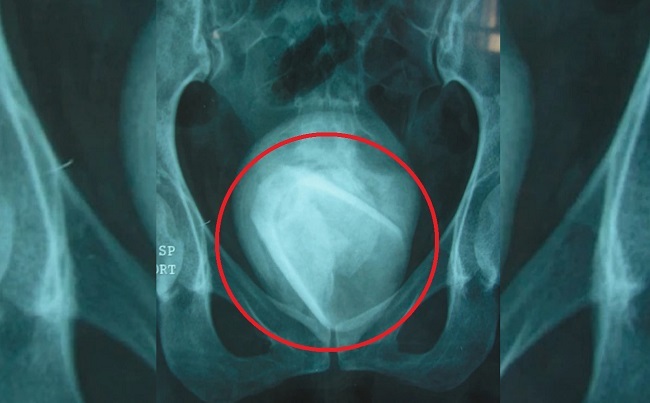

Неназванная 45-летняя женщина из Туниса обратилась в больницу с жалобами на боль, неприятные ощущение в низу живота и "подтекание" мочи. Эти симптомы были похожи на симптомы инфекции мочевыводящих путей, однако врачи на всякий случай послали ее на рентген. На снимке они увидели крупный инородный предмет в мочевом пузыре, похожий формой на ... стакан для питья. Когда врачи стали расспрашивать женщину о том, как в ее теле мог оказаться этот предмет, она призналась, что еще четыре года назад использовала стеклянный стакан в качестве секс-игрушки. При этом она вставила его в уретру (мочеиспускательный канал). Сложно сказать, как такой стакан мог пройти через уретру обычных размеров и насколько это было болезненно, однако в итоге стакан оказался внутри мочевого пузыря и при этом женщина лишь спустя четыре года озаботилась этой проблемой. Этот случай был недавно опубликован в медицинском журнале "Urology Case Reports". Предполагается, что данная пациентка практиковала так называемое зондирование уретры - рискованные действия, включающие в себя введение разнообразных предметов в уретру, чтобы усилить сексуальное удовольствие и возбуждение. Иногда подобным занимаются люди, имеющие проблемы с психическим здоровьем, но в отчете отмечается, что "мотивы, наиболее часто связанные с наличием инородных тел в мочевом пузыре, имеют сексуальный или эротический характер"

При взятии анализа крови выяснилось, что у нее был более высокий, чем обычно, диапазон эритроцитов, что указывало на то, что организм боролся с какой-то инфекцией. При операции по удалению инородного тела выяснилось, что стеклянный стакан за годы нахождения внутри мочевого пузыря покрылся толстой минеральной коркой, из которой обычно состоят мочевые камни. Когда инородное тело было извлечено, врачи раскололи камень и обнаружили внутри неповрежденный стеклянный стакан. Через два дня после операции женщина настолько хорошо себя чувствовала, что ее было решено выписать домой.